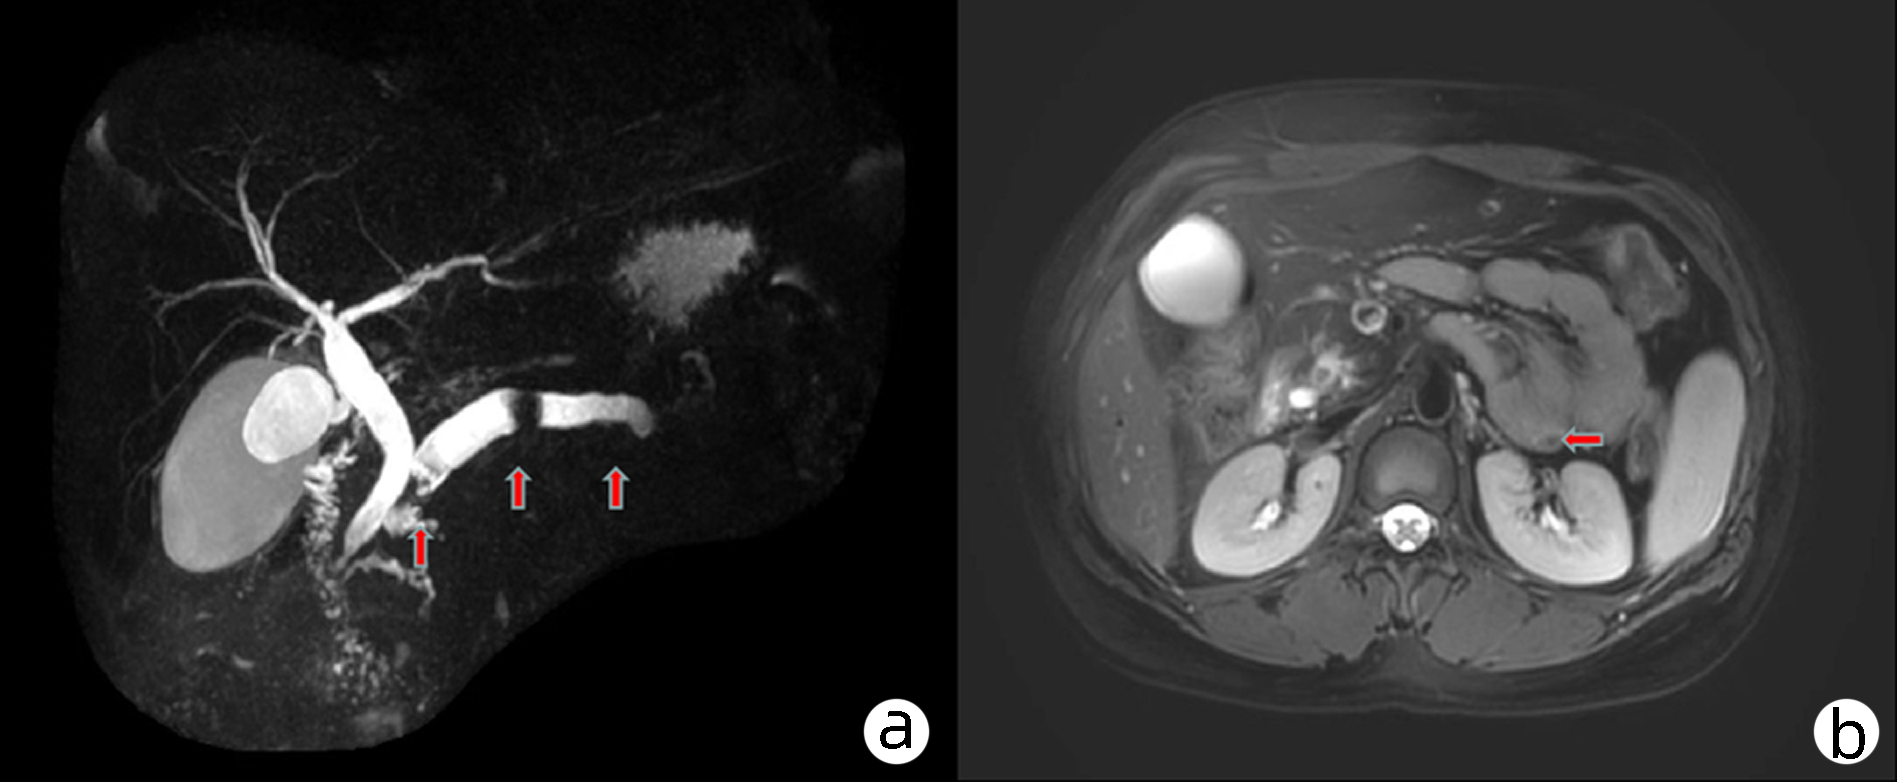

Sepsis with spontaneous splenic rupture and hemorrhage: A case report

Zhou LIU, Wenfang XIA, Liying ZHAN, Xiaoyu FANG, Liang ZHANG, Na ZHAN, Rong YU, Li HANG, Lei ZHU

2023, 39(8): 1926-1931. DOI: 10.3969/j.issn.1001-5256.2023.08.024

Abstract(1289) HTML (293) PDF (4249KB)(98)

Abstract:

Severe infections due to sepsis often result in multi-organ insufficiency, such as cardiac insufficiency, renal insufficiency, hypohepatia, septic encephalopathy, coagulation dysfunction etc. Severe infections not only cause inflammatory storm, but also induce spleen abscess, and even combined with spontaneous splenic rupture hemorrhage. Spontaneous splenic rupture has an insidious onset, usually without a history of trauma, and is easily missed diagnosis. In this case, the patient with sepsis had sudden onset of abdominal pain and progressive decrease in hematocrit, thus the abdominal CT was immediately performed. The perisplenic mixed high-density shadow indicated splenic hemorrhage. After consultation with the department of hepatobiliary surgery, emergency dissection was performed. Splenic hematoma and laceration were found during the operation, thus total splenectomy was conducted. Pathological indicated chronic inflammatory cell infiltration of spleen, spleen abscess with bleeding. After operation, the patient's hematocrit was stable, abdominal pain improved significantly, and he was discharged from hospital after systematic therapy.